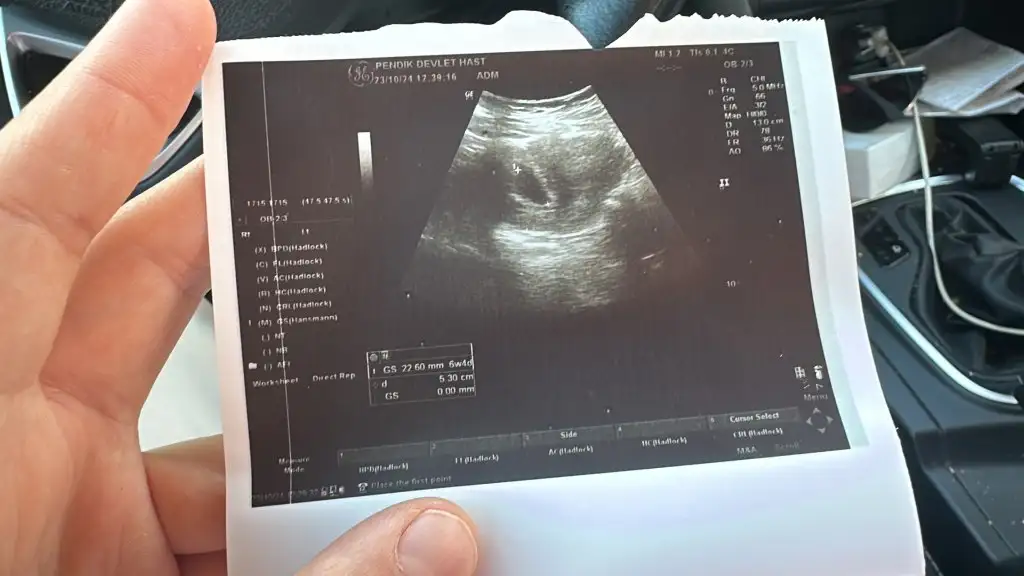

Gözünüz aydın :) kaç haftalıksınızGünaydın kızlar doktordan yeni çıktım. Sağlık ocağına gitmiştim muayene oldum kese 22mm bişeyler var içinde ama makinalar kötü net göstermiyor dedi haftaya gel kalbini duyarız dedi , bulantı içinde ilaç yazdı